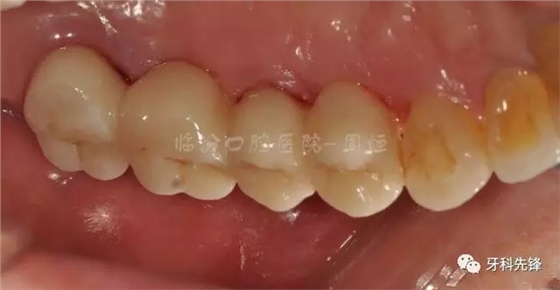

圖29術(shù)后頰面照

640.webp (33).jpg